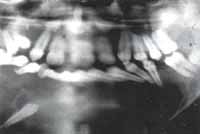

Fig. 16A – Fig. 16B En las proyecciones lateral y panorámica se puede observar la extensa lesión quística que produce deformidad facial y compromiso importante de casi todas las estructuras dentarias del maxilar inferior además del canino retenido y su desplazamiento basal.